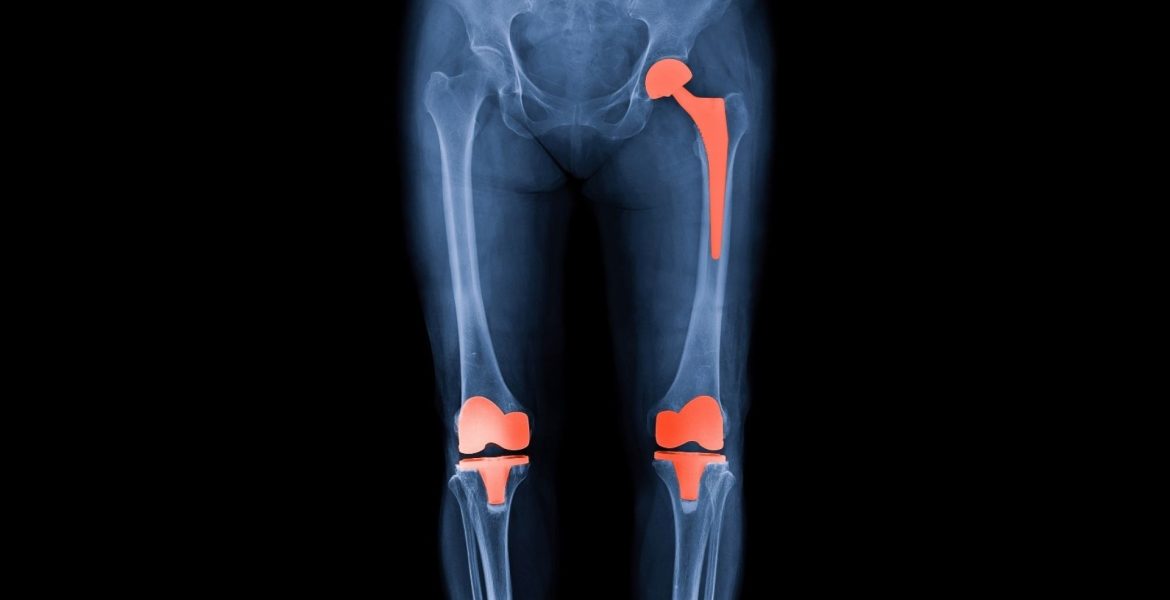

Diz, Kalça Protezi

EKLEM PROTEZLERİ